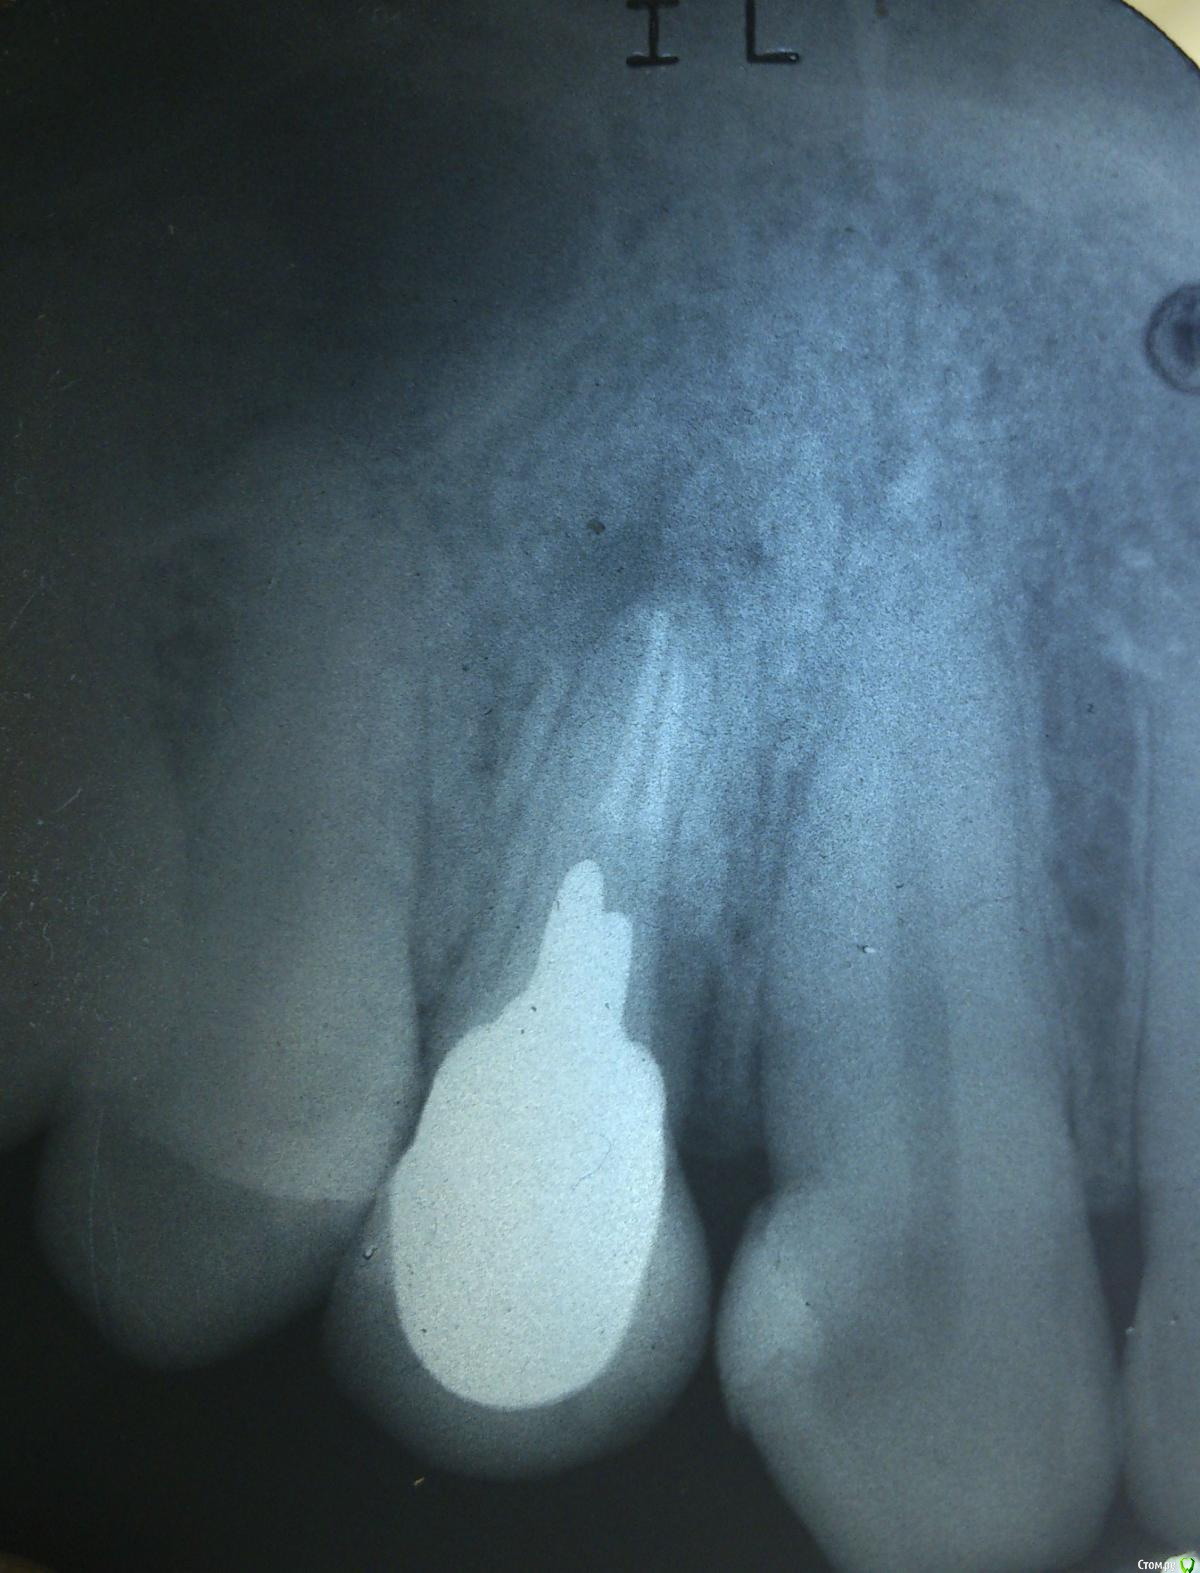

roman99 Опубликовано 21 мая, 2015 Поделиться Опубликовано 21 мая, 2015 Добрый день!Болит зуб под коронкой 5-й день, врач прописал цифран 500 мг 2 раза в день ( 5 дней) и супрастин на ночь ( 3 дня). Боль адская при надкусывании. Подскажите что делать? Приложил снимки зуба. Ссылка на комментарий

AlexanderGudkov Опубликовано 21 мая, 2015 Поделиться Опубликовано 21 мая, 2015 Снять коронку, удалить вкладку, перелечить каналы и по-новой протезировать, если все получится. Ну или удалить сразу зуб Ссылка на комментарий